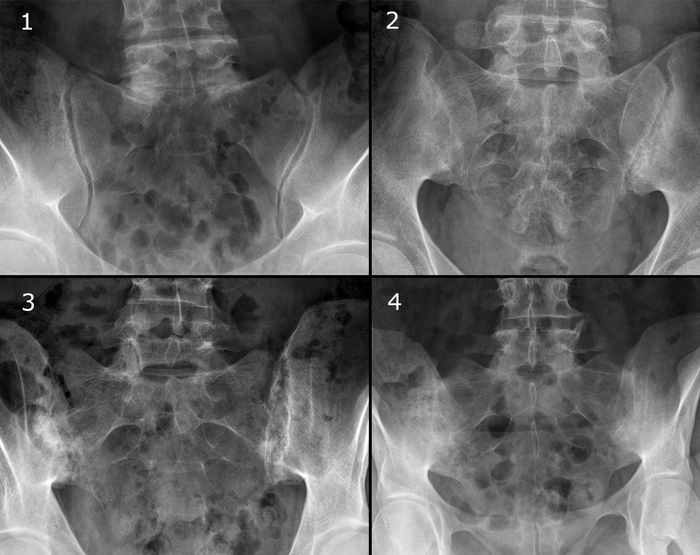

Рентгенологические градации сакроилиита в соответствии с модифицированными Нью-Йоркскими критериями диагноза англизирующего спондилита:

0 стадия - Отсутствие изменений

1 стадия - Подозрение на наличие изменений (отсутствие конкретных изменений, смазанность субхондрального слоя).

2 стадия - Минимальные изменения (небольшие локальные области с эрозиями или склерозом, сужение или неравномерность суставной щели.)

3 стадия - Безусловные изменения (умеренный или значительный сакроилиит с эрозиями, склерозом, расширением, сужением щели или частичным анкилозом)

4 стадия - Далеко зашедшие изменения (полный анкилоз)

Примеры сакроилиита на КТ,МРТ: